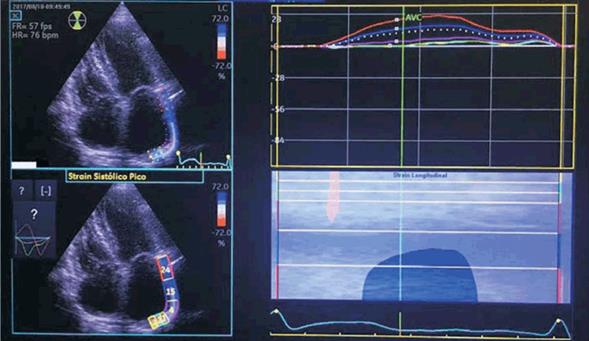

El strain de la AI usando speckle tracking es una innovadora e interesante propuesta, que si bien ha dado resultados contradictorios en distintos artículos publicados, la mayoría coinciden en su utilidad, especialmente al usar strain longitudinal33,34. El strain auricular izquierdo obtenido en vista apical de 4 cámaras es una medida de deformación que es inversamente proporcional a la presión auricular35). El valor del pico sistólico ( o en fase reservorio) corresponde a la sístole ventricular compatible con la fase diastólica auricular36(figura 2). La afectación de este valor demuestra una alteración en el llenado auricular, que refleja indirectamente un alto contenido fibrótico37. Los valores pico menores a 30% indican afectación significativa38. Kuppahally y colaboradores demostraron que la fibrosis de la AI valorada por resonancia magnética tiene correlación significativa con el strain en pico sistólico39. Como describen Motoki H40 y colaboradores, un valor de strain longitudinal global disminuido es un predictor de recurrencia posablación.